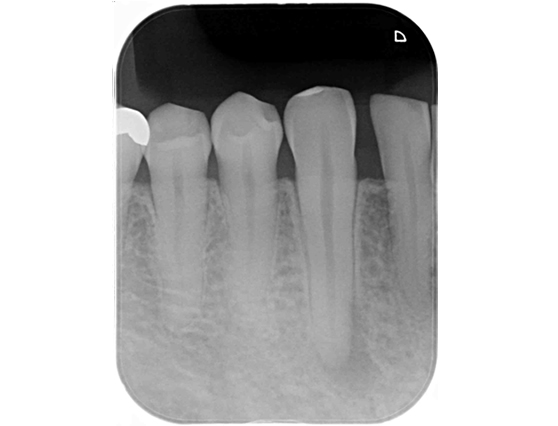

根管治療 症例7

治療前